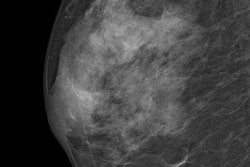

Radiologists have known for a long time that dense breasts are challenging to image with mammography. In addition, dense breasts bring down screening sensitivity for an entire program. German researchers have a solution for how to fix that. Read more.

There's been a lot of talk about contrast agents: How safe are they? When is the best time to use them? Another group from Germany answered all those questions. They found intravenous gadoteric acid is a safe and effective contrast agent for use in MR mammography. Adverse events were rare, and image quality was good to excellent.

Also in your Women's Imaging Community, we have news from leading researcher Dr. Christiane Kuhl. She gave an interview about what the future holds for breast cancer detection. In her opinion, breast screening with MRI is the way forward. What does that mean and what else did she have to say? Find out.

In terms of breast cancer screening, there are two stories you won't want to miss. First, the European Society of Breast Imaging along with 30 national bodies released a position paper on breast cancer screening. The goal of the paper is to achieve some clarity in the contentious debate over who should receive breast screening, according to lead author Dr. Francesco Sardanelli.